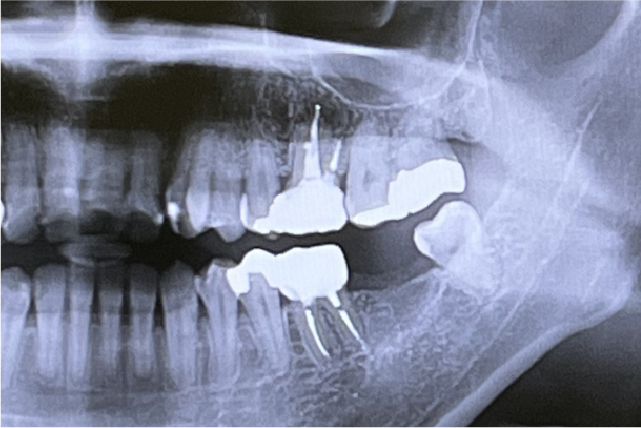

視診では確認できない、歯と歯の間や奥歯の虫歯を発見するために、6歳以降のお子さまは年に1度、レントゲン撮影を行います。

定期的な口腔内スキャナーによる検査で、虫歯や歯ぐきの腫れ、歯並びや歯の生え替わりの変化を一目で確認することができます。